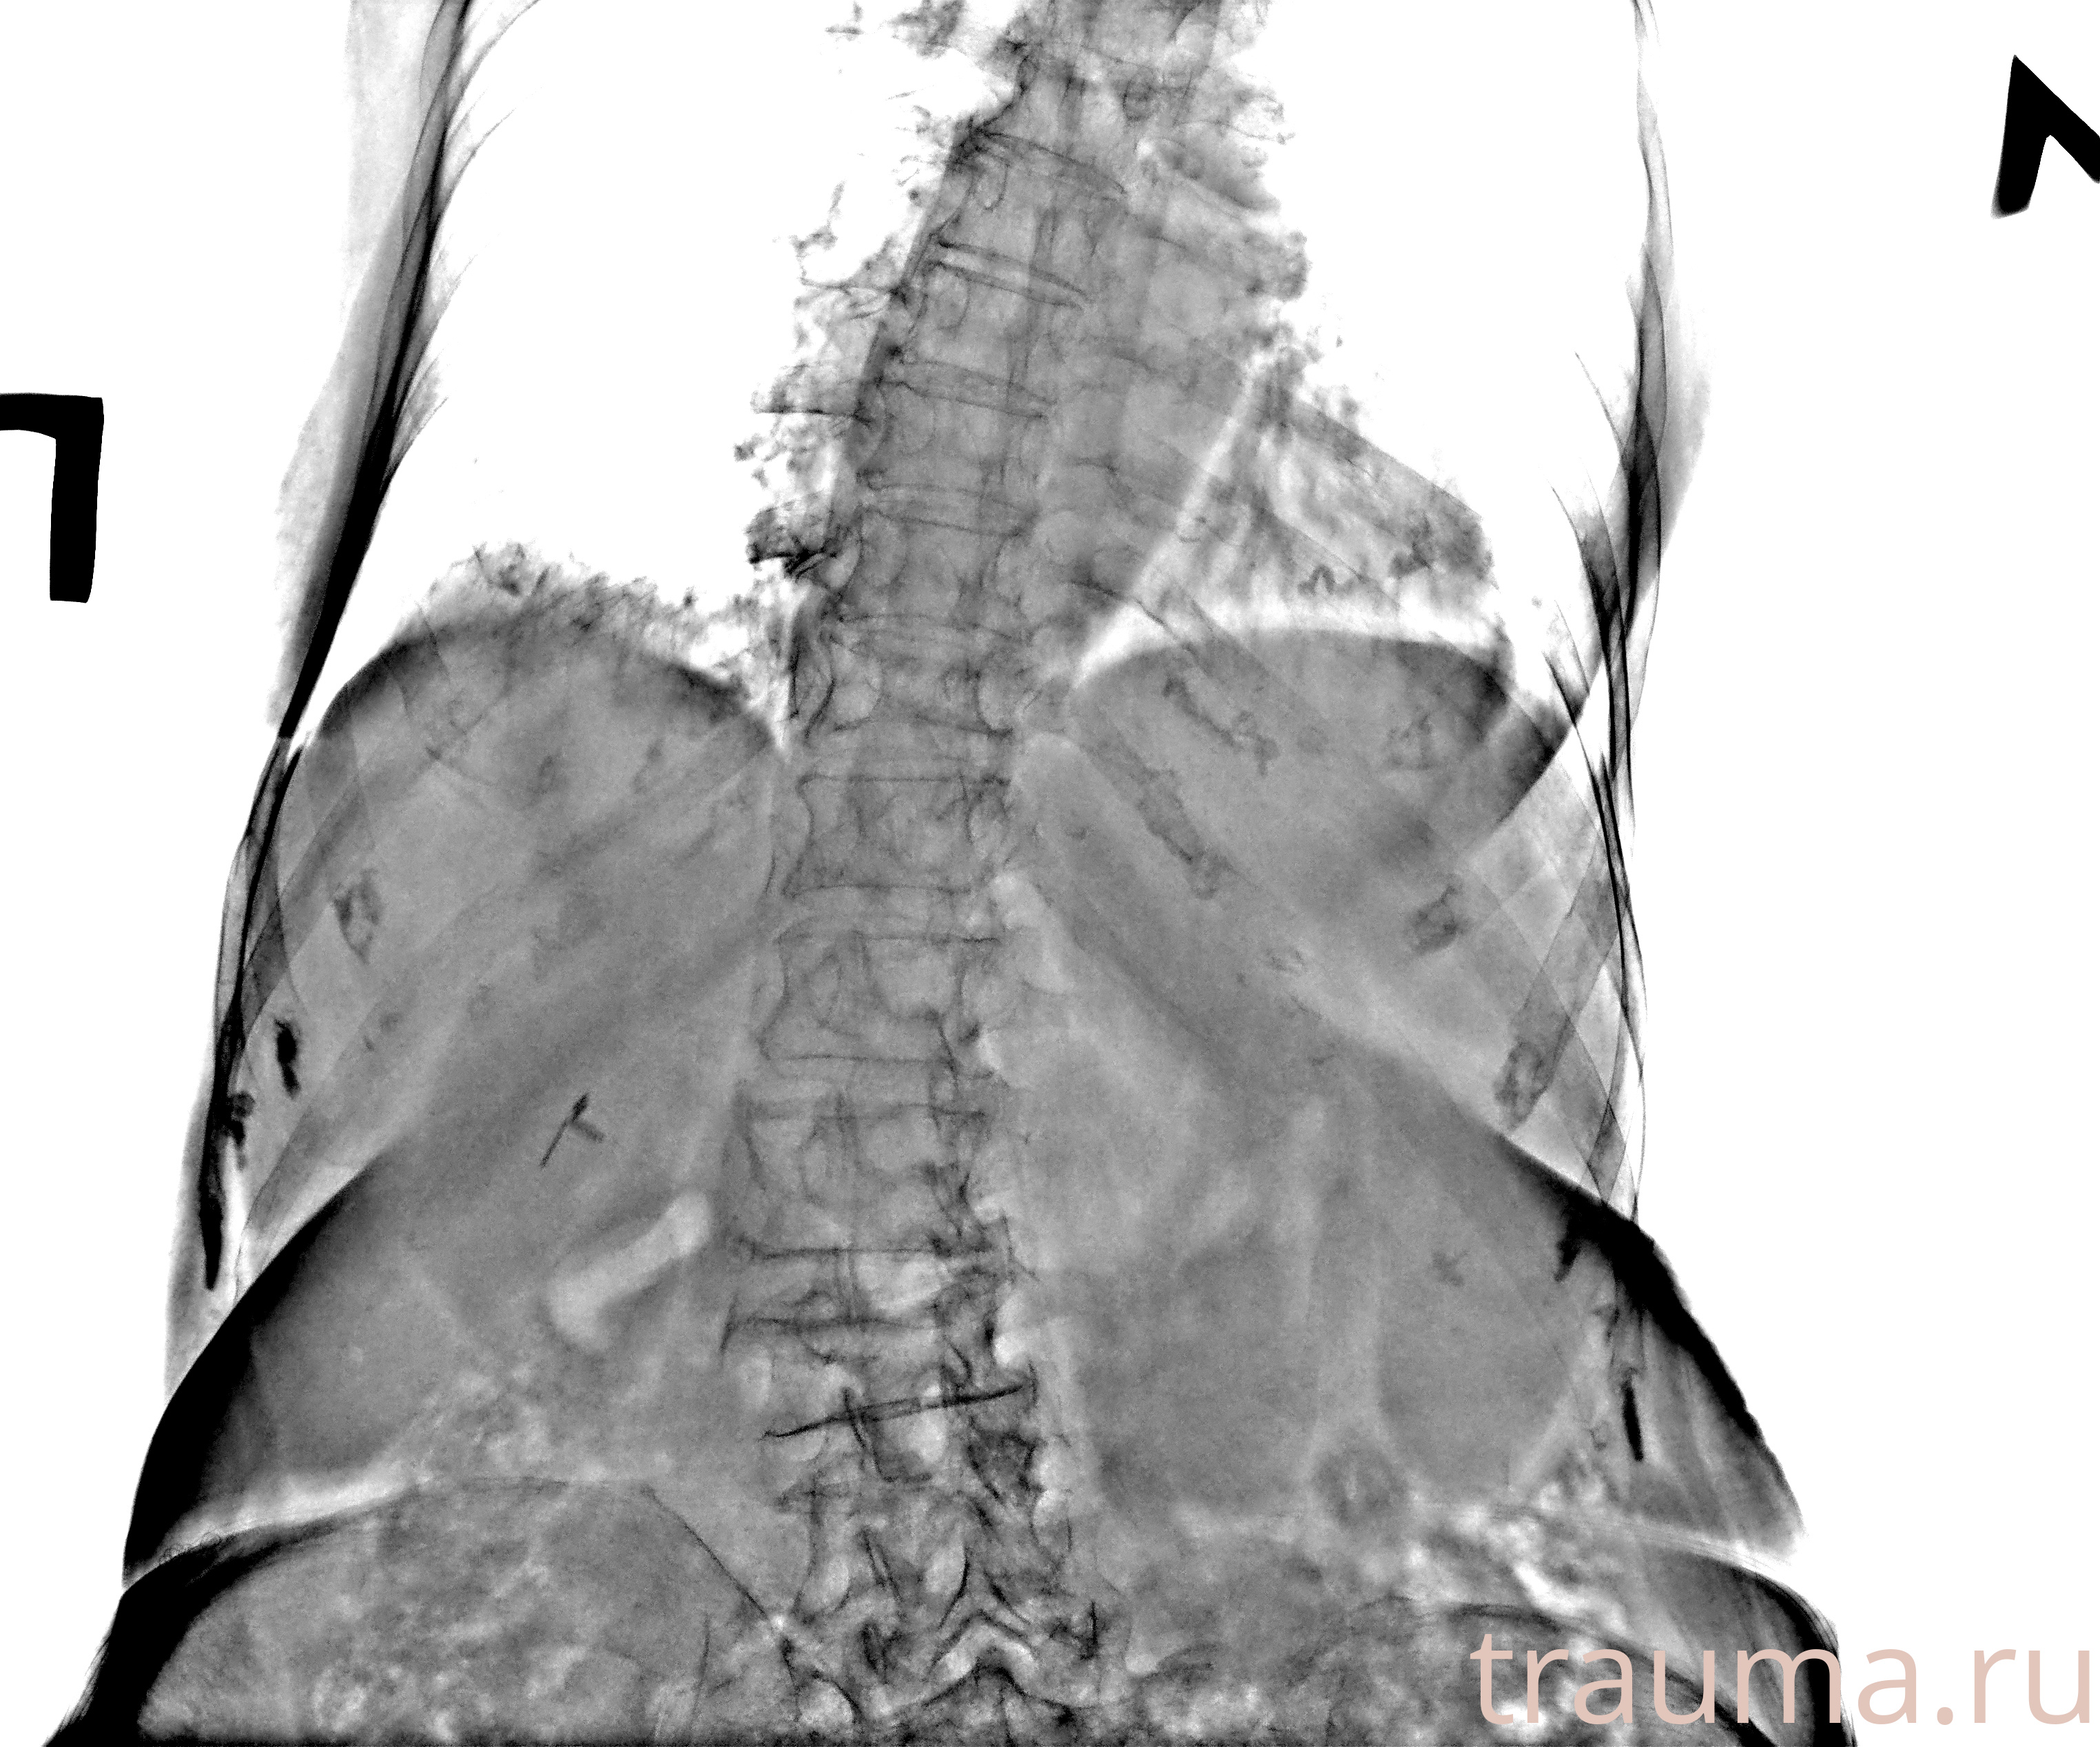

Рентген на дому: по вашему адресу приезжает врач-рентгенолог, травматолог-ортопед с мобильным рентгеновским аппаратом, проводит диагностику травмы или заболевания, делает необходимые рентгенограммы, дает рекомендации по дальнейшему лечению. Получить качественные снимки в домашних условиях возможно благодаря уникальной методике, разработанной МосРентген Центром для института  Склифосовского